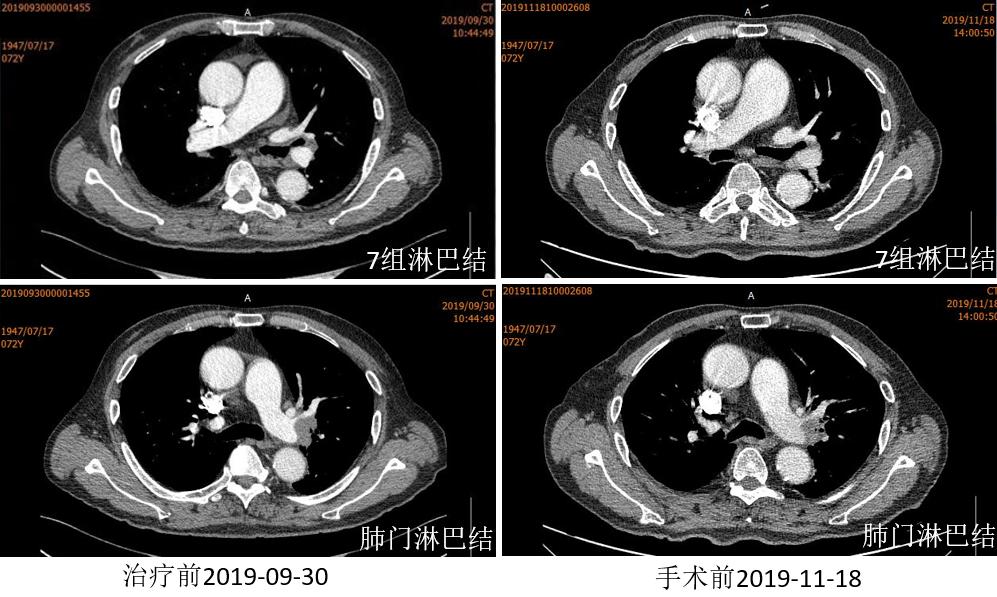

胸部CT

外周淋巴结CT